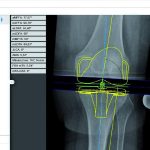

mediCAD Hectec GmbH, Landshut, Germany is pleased to announce that they have signed strategic partnership with TOYO Corporation as of December 21st, 2018. TOYO Corporation will be the exclusive sales partner representing the company’s preoperative planning solution mediCAD® in Japan. TOYO Mehr